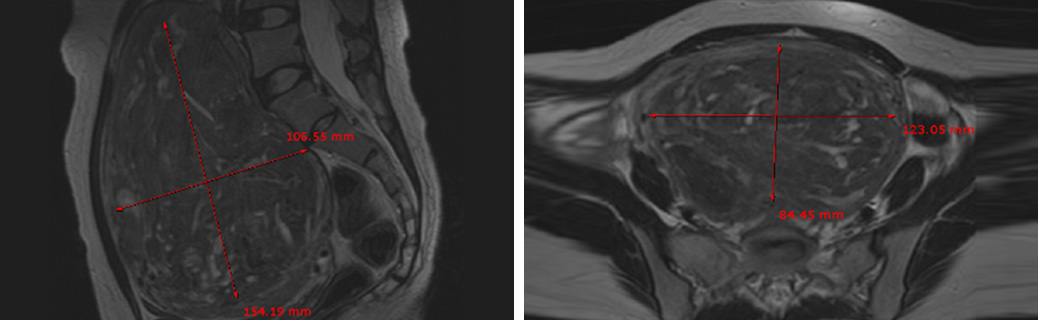

질출혈과 생리과다 및 복부에만져지는 거대 자궁근종으로 자궁근종 하이푸 치료를 위해 내원하였습니다.

하이푸 시술전 MRI사진상 척추와 복벽을 밀고있는 14cm의 혈류가 풍부한 거대 자궁근종이 관찰됩니다. 자궁근종 하이푸 치료는 자궁근종 부위만 선택적으로

치료하는 시술로 자궁근종 전체적으로 자궁근종 하이푸 치료하였고, 14cm 거대 자궁근종 하이푸 치료시간은 164분이 소요되었습니다.

(Uterine Myoma Hifu treatment time 164min)